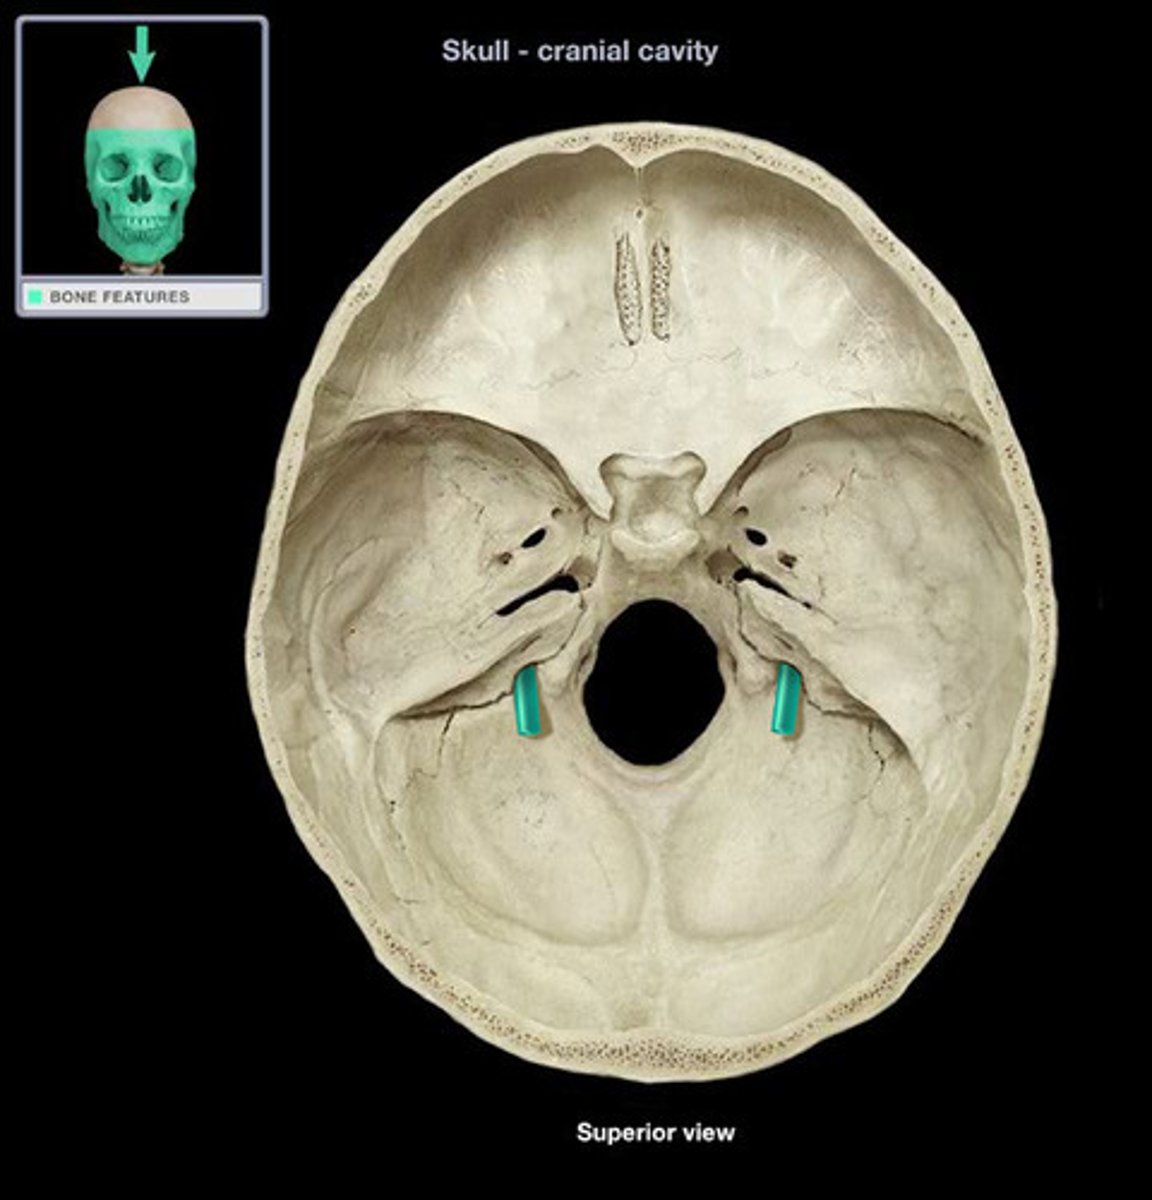

internal acoustic meatus

passage for facial (VII) and vestibulocochlear (CN VIII) nerves

jugular foramen

opening that transmits the internal jugular vein and cranial nerves IX, X, and XI

hypoglossal canal

hole that transmits the hypoglossal nerve (CN XII)